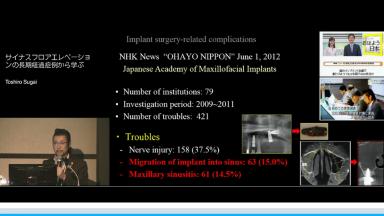

サイナスフロアエレベーションの長期経過症例から学ぶ本講演では、サイナスフロアエレベーションに関するトラブル、そのトラブルを防ぐための診査・診断・意思決定、四半世紀の臨床を通じて臨床例・長期経過症例から学ぶこと、そしてサイナスフロアエレベーション部位に埋入されたインプラントの臨床成績について報告があった。まずサイナスフロアエレベーションにおけるトラブルを防ぐための診査・診断として上顎臼歯部の欠損状態と解剖学的形態を把握し、インプラント治療の適応となればその適切なアプローチの仕方を検討することが重要である。更には移植材料について、文献を通じてそれぞれの特徴や生存率に関して報告された。サイナスフロアエレベーションは正しい診断と適切な外科手技の元に行えば上顎臼歯部における骨造成を伴う方法として非常に確立された方法と考えられると結んでいる。

- サイナスフロアーエレベーションのトラブルを防ぐための診査診断